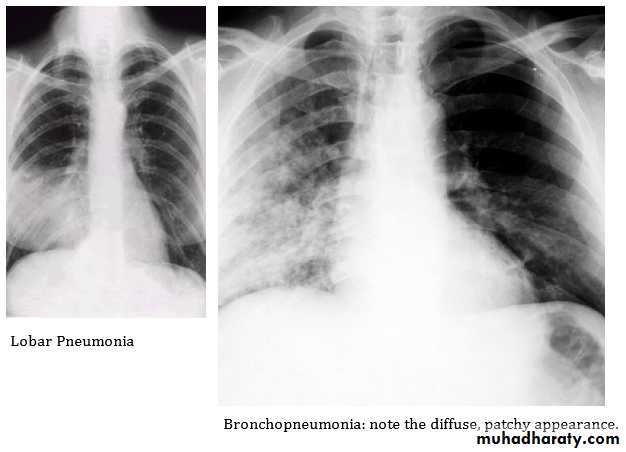

2- Morpological classification: Bronchopneumonia vs. lobar pneumonia(which may be segmental, lobar or multilobar).

Lobar pneumonia; is a radiological and pathological term referring to homogeneous consolidation of one or more lung lobes, often with associated pleural inflammation

Bronchopneumonia; refers to more patchy alveolar consolidation associated with bronchial and bronchiolar inflammation often affecting both lower lobes

Radiological examination

In lobar pneumonia, a homogeneous opacity localized to the affected lobe or segment usually appears within 12-18 hours from the onset of the illness.If a complication such as parapneumonic effusion, intrapulmonary abscess formation, or empyema is suspected.

Chest X-ray shows mottled opacities in both lung fields, chiefly in the lower zones.